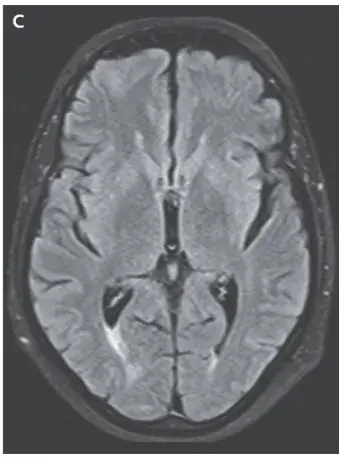

La resonancia magnética (RM) cerebral ponderada en T2 mostró una señal hiperintensa en la sustancia blanca cortical y subcortical, hallazgos consistentes con **edema vasogénico** (imágenes A y B). Los hallazgos de la angiografía por RM arterial y venosa fueron normales.

Se retiró el medicamento (ciclosporina) y los síntomas del paciente y los hallazgos de la resonancia magnética se resolvieron (Imagen C).